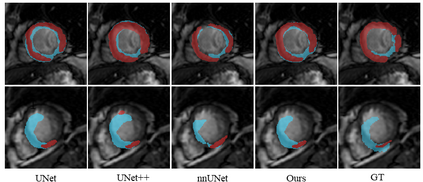

Multi-sequence cardiac magnetic resonance (CMR) provides essential pathology information (scar and edema) to diagnose myocardial infarction. However, automatic pathology segmentation can be challenging due to the difficulty of effectively exploring the underlying information from the multi-sequence CMR data. This paper aims to tackle the scar and edema segmentation from multi-sequence CMR with a novel auto-weighted supervision framework, where the interactions among different supervised layers are explored under a task-specific objective using reinforcement learning. Furthermore, we design a coarse-to-fine framework to boost the small myocardial pathology region segmentation with shape prior knowledge. The coarse segmentation model identifies the left ventricle myocardial structure as a shape prior, while the fine segmentation model integrates a pixel-wise attention strategy with an auto-weighted supervision model to learn and extract salient pathological structures from the multi-sequence CMR data. Extensive experimental results on a publicly available dataset from Myocardial pathology segmentation combining multi-sequence CMR (MyoPS 2020) demonstrate our method can achieve promising performance compared with other state-of-the-art methods. Our method is promising in advancing the myocardial pathology assessment on multi-sequence CMR data. To motivate the community, we have made our code publicly available via https://github.com/soleilssss/AWSnet/tree/master.